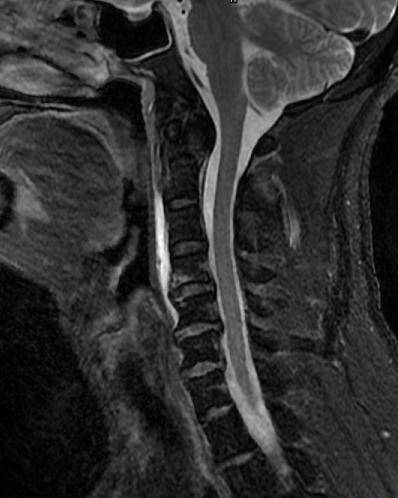

术中,手术团队对王先生颈部重要的组织结构均进行了较好的保护,而且一次性成功的置入空心钉固定骨折断端。手术持续了近5个小时,术后王先生症状明显缓解,无神经损伤。术后复查X线显示齿状突复位,螺钉位置良好。目前王先生已顺利出院,并对北京友谊医院骨科中心的服务进行了高度的评价。

术后显示齿状突复位,螺钉位置良好